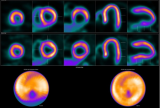

新型Tau PET示踪剂具有高灵敏度和特异性,可识别早期阿尔茨海默病

根据《The Journal of Nuclear Medicine》9月刊上发表的一项研究表明,一种新型Tau PET放射性示踪剂18F-SNFT-1被发现比现有的Tau PET放射性示踪剂更能在早期阶段识别阿尔茨海默病。在正面比较中,与临床使用的第二代Tau PET示踪剂相比,18F-SNFT-1具有更好的脑部药代动力学,并且对阿尔茨海默病Tau蛋白病变显示出更高的亲和力和选择性。